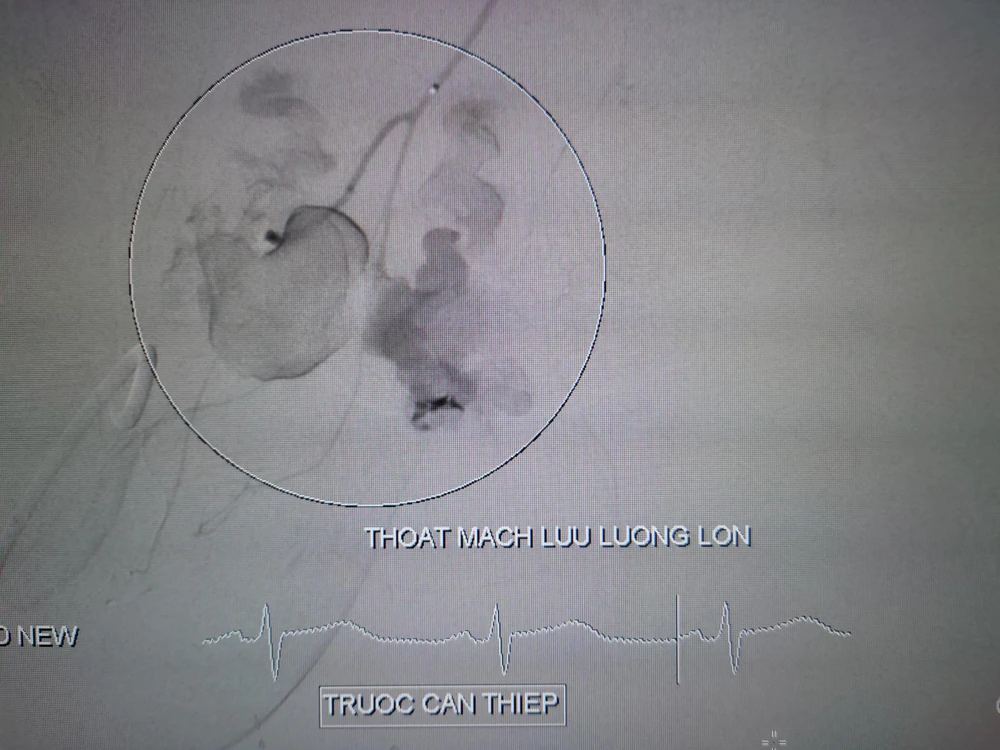

Hình ảnh trước và sau can thiệp nội mạch cho bệnh nhân bị tường đè nguy kịch. Ảnh: BVCC

Bác sĩ đã giải quyết ổ chảy máu lưu lượng lớn vùng chậu bằng phương pháp can thiệp nội mạch, dẫn lưu màng phổi, nắn khớp vai và phẫu thuật tắc động mạch cánh tay.

Sau đó, các bác sĩ can thiệp mạch chụp mạch số hóa xóa nền mạch máu vùng chậu phát hiện ổ thoát mạch từ nhánh động mạch chậu trong (T), tiến hành nút mạch cầm máu ổ thoát mạch lưu lượng lớn với thời gian 10 phút.